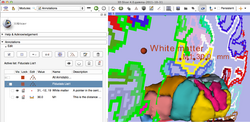

The community of Slicer developers is proud to announce the release of Slicer 4.0.

- Slicer 4.0 includes a major overhaul of the user interface, improved and simplified workflows for major tasks, simplified procedures for developers, and improved Python support.

Slicer is a community platform created for the purpose of subject specific image analysis and visualization.

- Multi-modality imaging including, MRI, CT, US, nuclear medicine, and microscopy

- Slicer 4.0 - New and Improved Modules